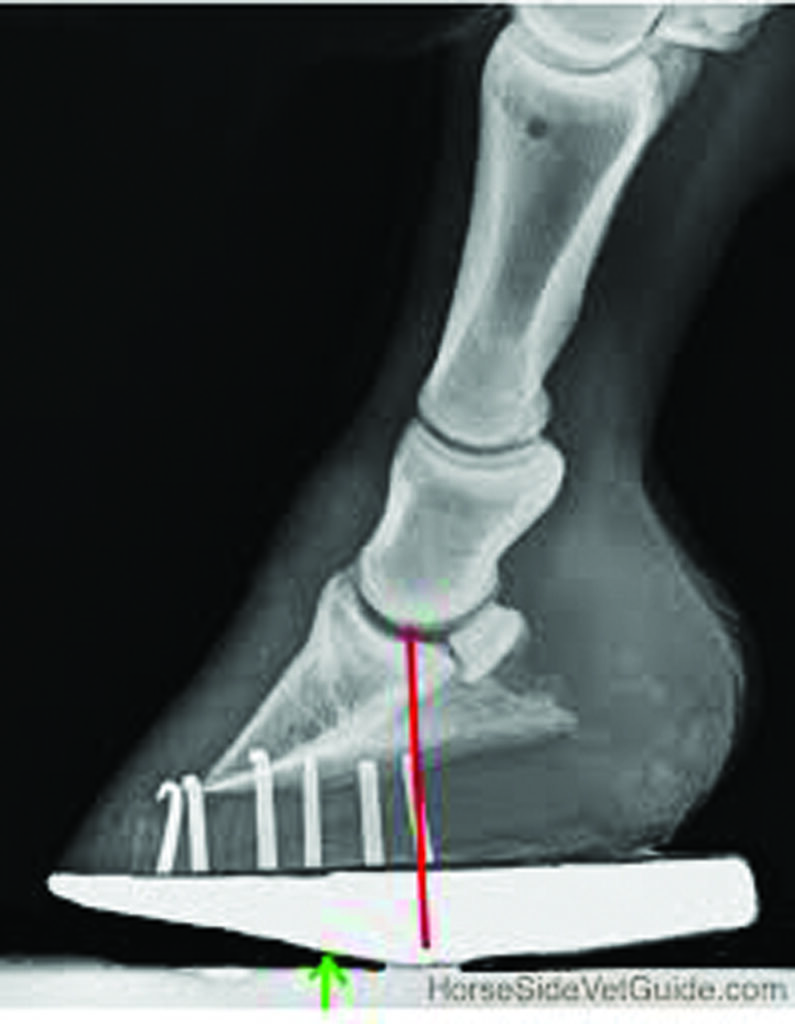

Radiograph showing mechanics of the roller motion shoe on the hoof, identifying one way to address Navicular Syndrome. The red line identifies the center of rotation of the coffin joint. The goal is to relieve stress on the heel and navicular apparatus and thus relieve pain, plus protect the area from direct trauma.